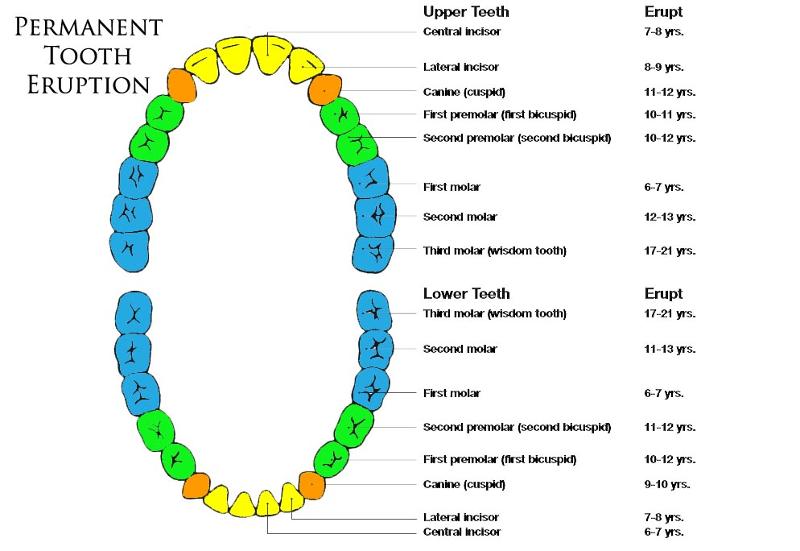

Deciduous Teeth

baby teeth

14

Permanent Teeth

Incisors (8)

Permanent Teeth FRONT

16

Canines (4)

Permanent Teeth

17

Premolars (8)

Permanent Teeth

18

Molars (12)

Permanent Teeth